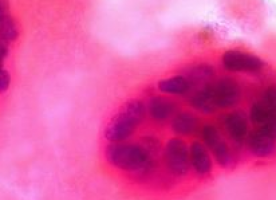

The primary endpoint of this study is pathological complete response (pCR) in breast and lymph nodes at the time of surgery.

The investigators concluded that the probability that the neratinib-containing regimen has a higher rate of pCR than control therapy in HR-negative, HER2-positive breast cancer (one of the 10 biomarker signatures) is 95 percent and its predictive probability of success in a future, randomised, 300-patient phase III trial is 79 percent.